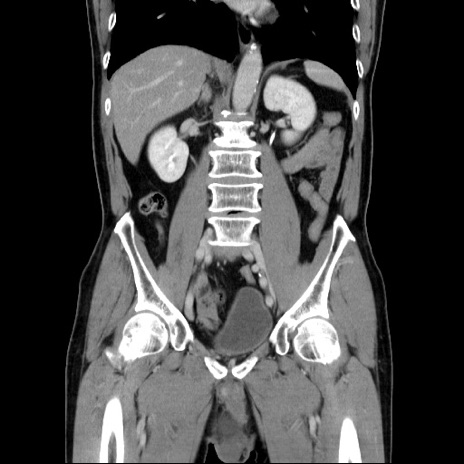

症例34(冠状断像)

【症例】60歳代 男性

【主訴】右鼠径部膨隆

【現病歴】1年程前より右鼠径部膨隆あり。自己にて還納可能だったため放置していた。3時間前より右鼠径部の脱出を認め、還納困難となり受診。

【既往歴】高血圧

【身体所見】右鼠径部に小児頭大の膨隆あり。弾性硬であり、用手還納は困難。左鼠径部にも膨隆を認める。脱出はなし。